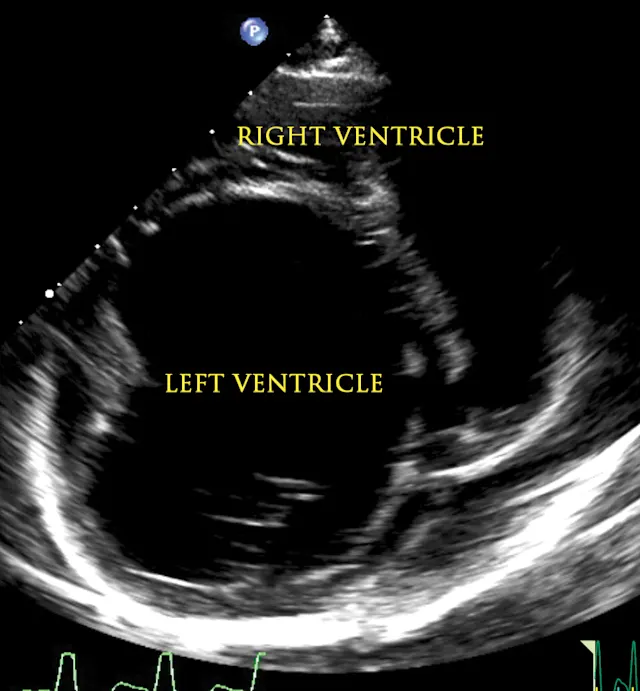

An echocardiogram and thoracic radiographs were obtained. The echocardiogram revealed decreased left ventricular (LV) wall thickness, severe dilation of the LV chamber (ie, eccentric hypertrophy), and severely reduced LV systolic function. Severe left atrial enlargement with a moderate degree of centrally directed left atrioventricular valve regurgitation (suspected functional) was observed. The left atrioventricular valve leaflets appeared normal in thickness with poor coaptation due to annular stretch. In addition, there was mild dilation of the right atrium and ventricle with a mild degree of right atrioventricular valve regurgitation. Results of echocardiography were consistent with dilated cardiomyopathy (DCM; Figures 1-4).2,3

Figure 1

2D echocardiographic image of the left ventricle from the right parasternal short axis view. There is decreased thickness of the LV walls and severe dilation of the LV cavity consistent with DCM.